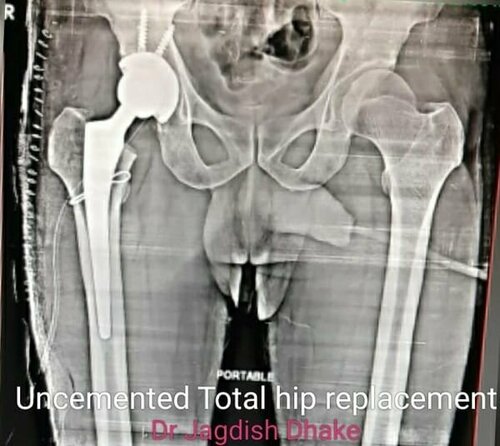

Total Hip Replacement | Dr. Jagdish Dhake

53 year male patient was suffering from avascular necrosis right Hip, he got operated by Dr. Jagdish Dhake - Orthopedic Surgeon in Bibvewadi with Unce...